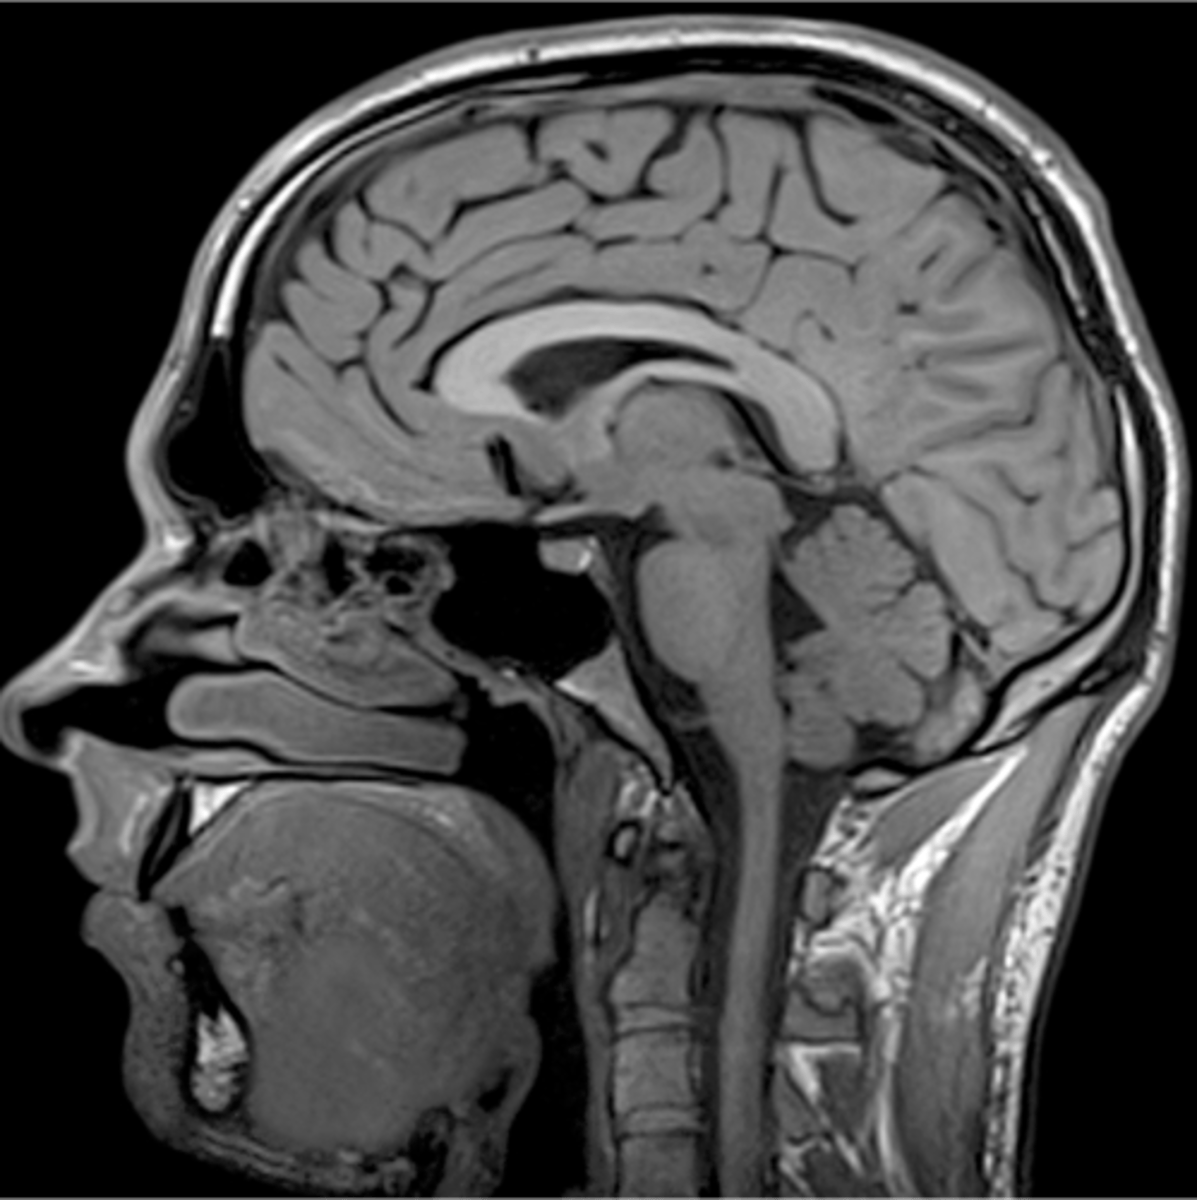

describe

normal MRI